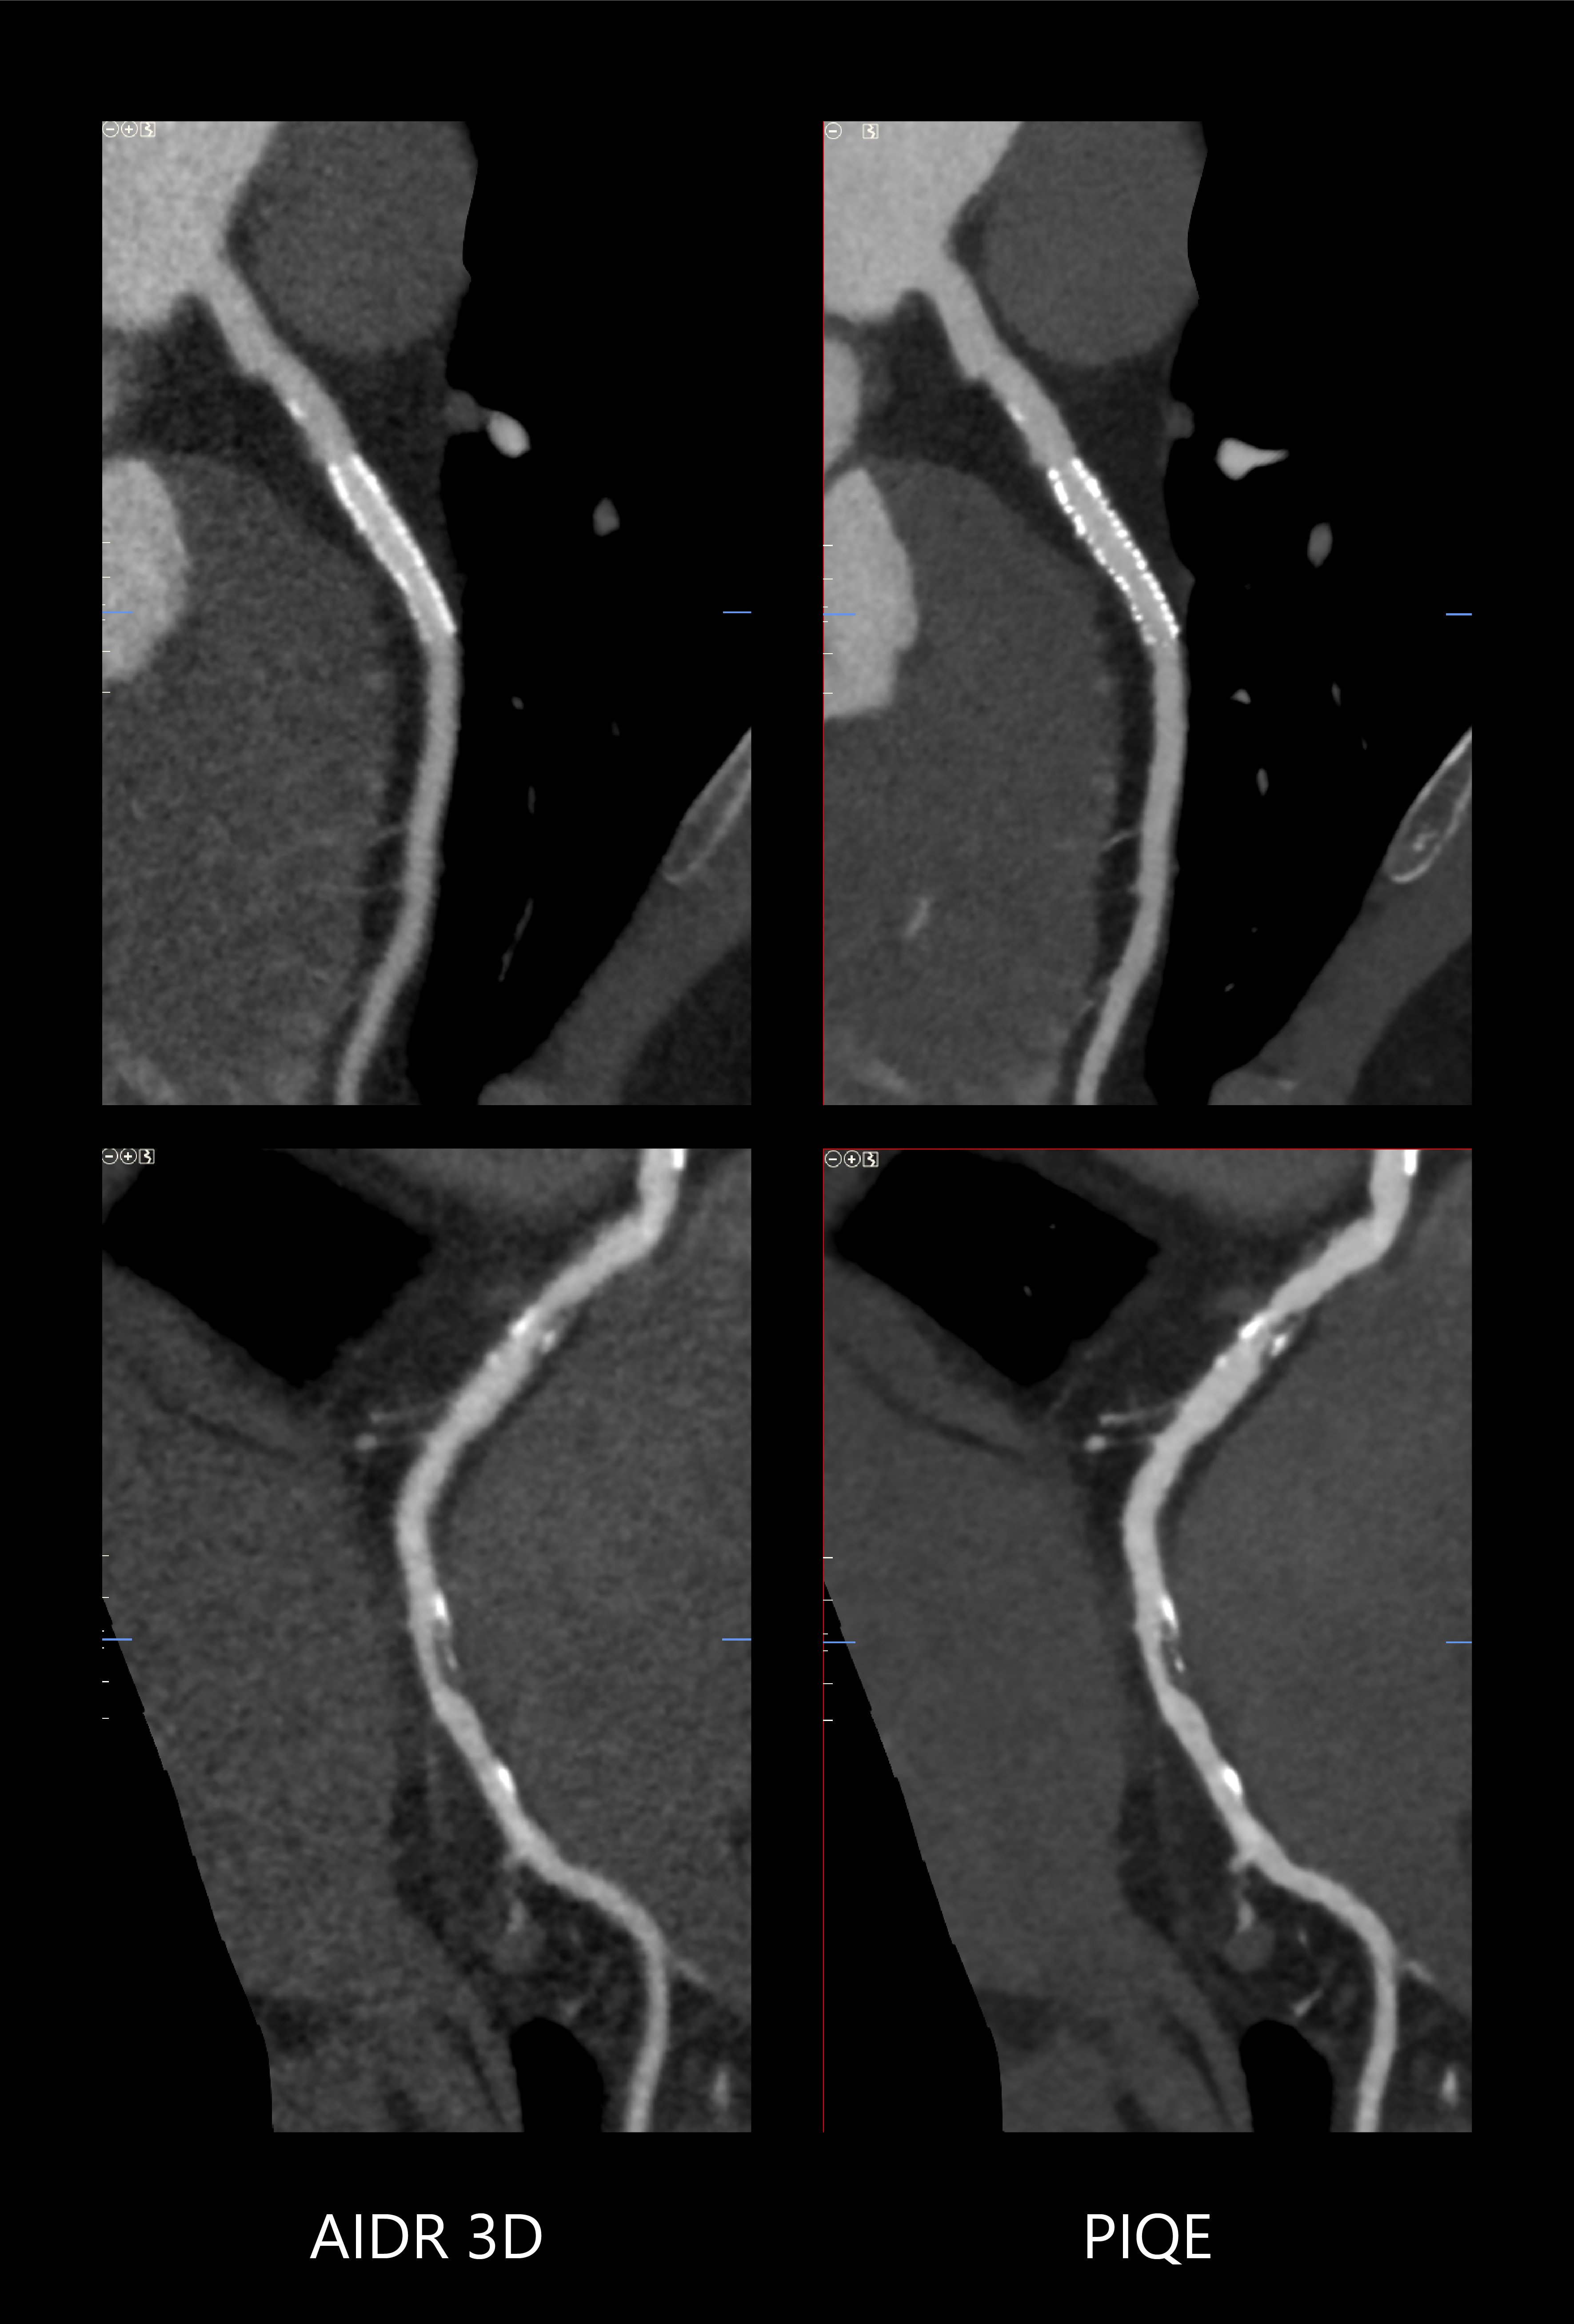

Precise IQ Engine (PIQE)

A new standard in cardiac clarity

PIQE provides improved spatial resolution and 45% reduced noise* for improved in-stent visualization with clear depiction of vessel lumen to evaluate neointimal hyperplasia and in-stent restenosis. The high contrast to noise properties of PIQE exams also provide better evaluation in heavily calcified coronary arteries with no loss of low contrast detectability* – and these benefits are provided without any additional dose.

Robust for all patients, ONE beat CTA examinations with PIQE offer:

-Sharper anatomical detail

-Reduced calcium blooming

-No additional dose

-Isophasic Uniformity